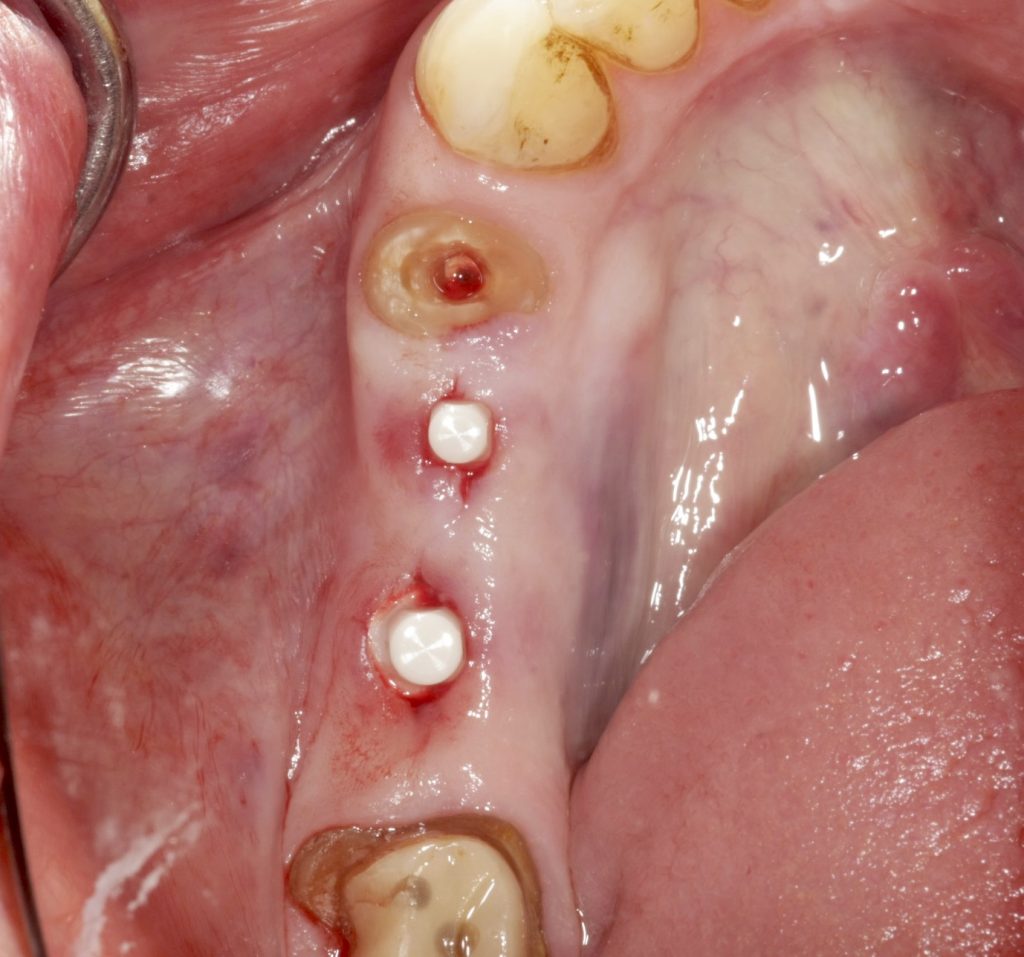

Autores: PRÓLOGO Asimismo, desde el punto de vista pedagógico, el profesional nobel en la materia tiene a su alcance la posibilidad de corregir cualquier posición implantaría en el ordenador, planear los provisionales y plasmarlos en la bio réplica antes de tocar al paciente a operar. Todos estos razonamientos nos llevan a presentar un caso de condiciones muy favorables para poner en práctica estos métodos como primer acercamiento a una Odontología Digital de alta calidad, con medios informáticos, que ya están presentes en la profesión de hoy en día, y será la protagonista única del futuro. Por otro lado, después de numerosos estudios que nos llevan a plantear el “gap” entre implante y pilar(abuttment), como principal responsable de la periimplantitis dado que la microbiota presente en el mismo es imposible de limpiar y en su presencia la cortical ósea reacciona reabsorbiéndose, nos ha llevado a utilizar implantes monobloc ya que los ejes implantarios y protéticos coincidían, y nos permitían su uso. Además, el circonio, ha mostrado a la luz de estudios muy recientes, una preservación y adhesión de los tejidos blandos superiores al titanio, tanto en su tratamiento de superficie de la rosca como a nivel gingival. DESARROLLO Paciente varón de 68 años, con antecedentes de radio/quimioterapia cinco años antes, con Rehabilitación Oral de los cuatro cuadrantes, con una Oclusión Mutuamente Compartida conservada, (REF.8) la que fracasa en el cuadrante 4, 19 años después. El mismo presentaba un puente de porcelana sobre circonio con pilares en 44 y 47, reemplazando el edentulismo de 45 y 46. Se produce la fractura del PM del 44, y ante una endodoncia antigua y corta, se decide implantar las zonas edéntulas, conservando temporariamente los pilares, hasta producida la oseointegración, para entonces también exodonciar el 44. DIAGNÓSTICO Tomamos impresiones del maxilar antagonista, Arco Facial Estático y realizamos montaje del mismo mediante la sistemática ARTEX. Producimos la relajación del músculo Pterigoideo Externo, para obtener la ORC (Oclusión en Relación Céntrica) mediante el método de Laminillas de Long, basado en el concepto de INERVACIÓN RECÍPROCA. Esto nos permitirá montar el maxilar inferior, tanto en su forma de: La primera para practicar la cirugía guiada y comprobar su eficacia, y el modelo de yeso para ser escaneado y confeccionar la GUÍA QUIRÚRGICA. La Biorréplica la obtenemos transformando los archivos DICOM que nos da el CBCT en archivos STL, y a partir de ellos, mediante una tecnología de PROTOTIPADO RÁPIDO, la obtención de un objeto físico en 3D a través de la aglutinación selectiva de una sucesión de capas de polvo. Procedemos a montar la biorrèplica y el modelo de yeso del caso. Podemos verificar la exactitud de las medidas del hueso residual en la bio réplica y compararlas con el scanner. Arrojando un resultado de 8,5 mm de cortical externa a cortical externa. Pudiendo también medir la distancia hasta el dentario. y comparar gracias a la ventana lateral de la biorréplica Dándonos 22mm de distancia. Con lo cual deducimos que implantes de 4,1mm por 12 mm serán perfectamente rodeados de hueso. Medimos también la distancia desde oclusal del antagonista, hasta el hueso desnudo. Lo mismo que, mediante la utilización de la guía radiológica, con un material radiolúcido colocado en gingival de la misma, podemos medir la altura de la encía. Con lo cual podemos calcular la altura del pilar. Es entonces cuando con el programa COC Diagnostix se realiza la programación final: Obteniendo no solo la ubicación, largo, ancho y ángulo de los implantes sino también los provisionales mediante CAD CAM. Ya entonces podemos hacer la práctica quirúrgica en la bio réplica, mediante la guía quirúrgica, instalando los implantes de prueba que no serán los de circonio, ya que la casa no cuenta con ellos, pero si otros de las mismas dimensiones. TRATAMIENTO Entramos ya en la cirugía propiamente dicha. Antisepsia de la zona a operar y zonas anexas. Comprobación del perfecto ajuste e inmovilidad de la G.Q. en boca durante la cirugía. Marcado de la encía y perforación de la cortical. Visión a través de la Guía de la mínima intervención anterior. Comprobación sin Guía. Incisión mínima mesio distal, para apartar y conservar encía queratinizada. Secuencia de drills, perforando a profundidad requerida Observación del Mínimo Trauma Implantes Strauman de Zirconio Monoblock en blíster y montádo en contrángulo reductor. Instalación controlando torque con contrángulo reductor. Comprobación clínica. Comprobación Radiográfica y con Guía. Toma de impresiones, y armado de modelos con técnicas de pasividad protética. Montaje. Resultado de las provisionales ejecutadas por CAD CAM Al no estar conformes con el resultado decidimos desechar dichas provisorias y optar por repetirlas. Nuevas provisorias realizadas mediante encerado convencional. Estado de los tejidos blandos. Provisorias en boca. Oclusión de Estímulo Inmediato. Ref.10: Carga inmediata .Alberto y Diego Bechelli. Comprobación mediante CBCT post operatorio Componentes del equipo (En la próxima presentación, mostraremos las coronas definitivas de porcelana sobre circonio, y la desoclusión provocada por una OCLUSIÓN MUTUAMENTE COMPARTIDA, sobre estos implantes y otros seis mas) REFERENCIAS

FIG: 1-2-3-4

Clinicamente es una boca rehabilitada y conservada en su totalidad, salvo este cuadrante que nos ocupa.

FIG:47-48-49

FIG:50-51-52-53-54

FIG:55

FIG:56

FIG:57

FIG:58

FIG:59-60-61-62

FIG:63

FIG:64-65

FIG.66-67

FIG:68-69

FIG.70-71

Fig:72-73-74-75-76-77-78-79-80-81